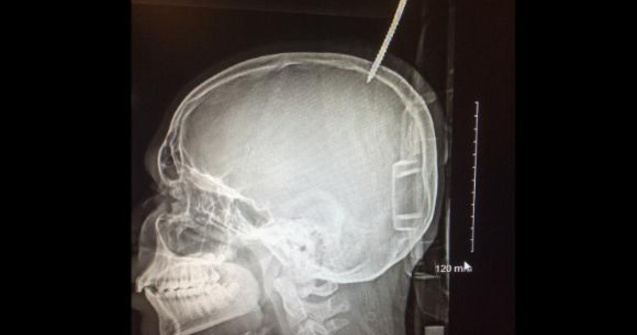

Darius Foreman, un baiat in varsta de 13 ani din Maryland, a ajuns de urgenta la spital, sambata, dupa ce a cazut in timp ce construia o casuta in copac si si-a perforat capul intr-un surub de 15 centimetri.